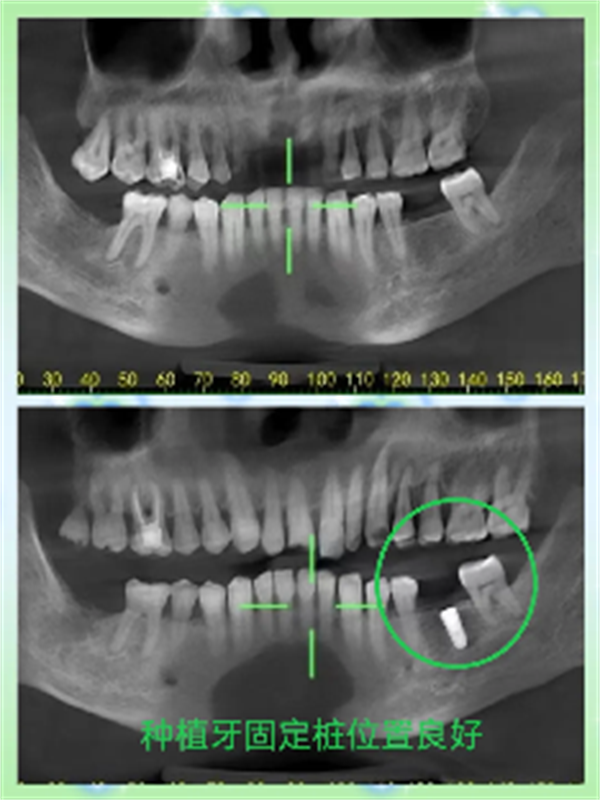

本网讯(通讯员:曾海燕、钟韬)7月23日,60岁的邓大哥在新宁县人民医院口腔科实施种植牙手术成功,复查种植牙位置良好,这是县人民医院口腔科开展的复杂疑难种植牙手术,标志着口腔科诊疗技术跃上新台阶。

邓大哥下颌双侧后牙缺失3年多,多次在外地医院口腔科就诊,种植没成功。近日,就诊于县人民医院口腔科。主治医师钟韬仔细检查,邓大哥的左下第一磨牙、右下第二磨牙缺失,牙槽嵴、咬合及牙周情况良好,拍摄CBCT后,评估满足种植条件,在上级医院专家陈炜会诊指导下完善手术方案。经积极术前准备,顺利完成左下第一磨牙区种植体植入,术后患者无任何不适。

全新口腔颌面锥形束计算机体层摄影设备(CBCT)